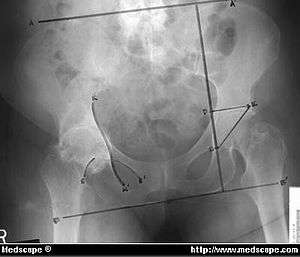

Protrusio acetabuli

| Right sided Protrusio acetabuli | |

Protrusio acetabuli is an uncommon defect of the acetabulum. The acetabulum is the socket that receives the femoral head to make the hip joint. The hip bone of the pelvic bone/girdle is composed of three bones, the ilium, the ischium and the pubis. In protrusio deformity, there is medial displacement of the femoral head in that the medial aspect of the femoral cortex is medial to the ilioischial line. The socket is too deep and may protrude into the pelvis.[1]